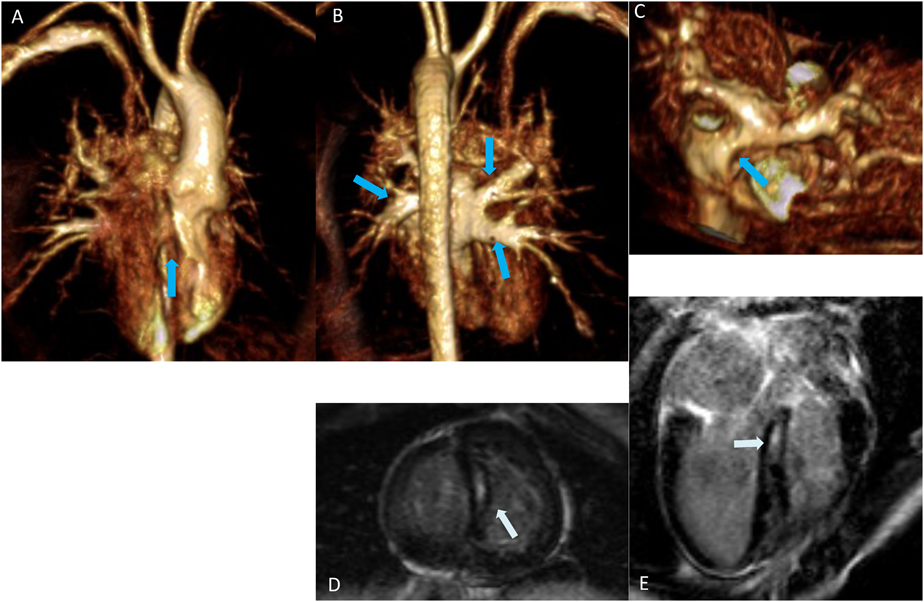

CMRでは心室全体が乳頭筋を含めて明瞭に描出されることで,ありのままの左右心室の姿(容積・拍出量・心筋重量・壁運動)が数値として表現される.撮影方法は一貫しており,検者によって評価断面がずれる心エコーと比較して再現性という点でも有利である.心室容積計測(解析)は一般にSimpson法(ディスク法)で行われる.左右心室ともに撮影できる短軸像(SA: Short-Axis)から求めるのが一般的で,各時相の心内外膜面をトレースすることで算出される(Fig. 1左).Mooijら23)は,60小児例のCMRから,右室拡張末期容積・心筋重量の検者内および検者間変動係数は6.4%および11.3%と低く,左室の3.6%から10.5%と変わらないと報告した.Grothuesら24)は,同係数を6.2%と8.7%と報告している.Clarkeら25)は,CHD50例でSA planeとaxial planeを比較し,右室収縮末期容積以外,両者に有意差なしと結論した.Blalockら26)は,ファロー四徴症(TOF)30例の右室容積・心筋重量・EF等が,同一症例の時期の異なる検査間でも高率に一致することを示し,経時的変化をとらえることができると主張した.

一方で,計測(解析)方法が適切でなければ,当然その値は不正確となる.誤差を生む最大の要因は,心基部(心房心室境界)および乳頭筋のトレース法にある.左右心室とくに右室では心基部の正確な同定には経験が必要である.基部を明瞭に判別するために,Axial planeでの撮影から容積計量する方法も推奨される(Fig. 1右).また,乳頭筋を一切無視する(内腔に含める)と左室については容積が6.5%増大するとされる27).特に心肥大の強い右室ではその影響が大きく,誤差が増大するため,pixel-intensityから乳頭筋を自動的に判別し内腔から除外できるソフトの使用が勧められている28)Fig. 2は自験例の心室容積をCMRとAngiogramで比較した図である.良好な相関が得られており,今まで用いてきた心カテによる心室容積と同様の臨床感覚で,より正確なCMRによる心室容積を用いることができる.

Fig. 1 Sample images of endocardial contours